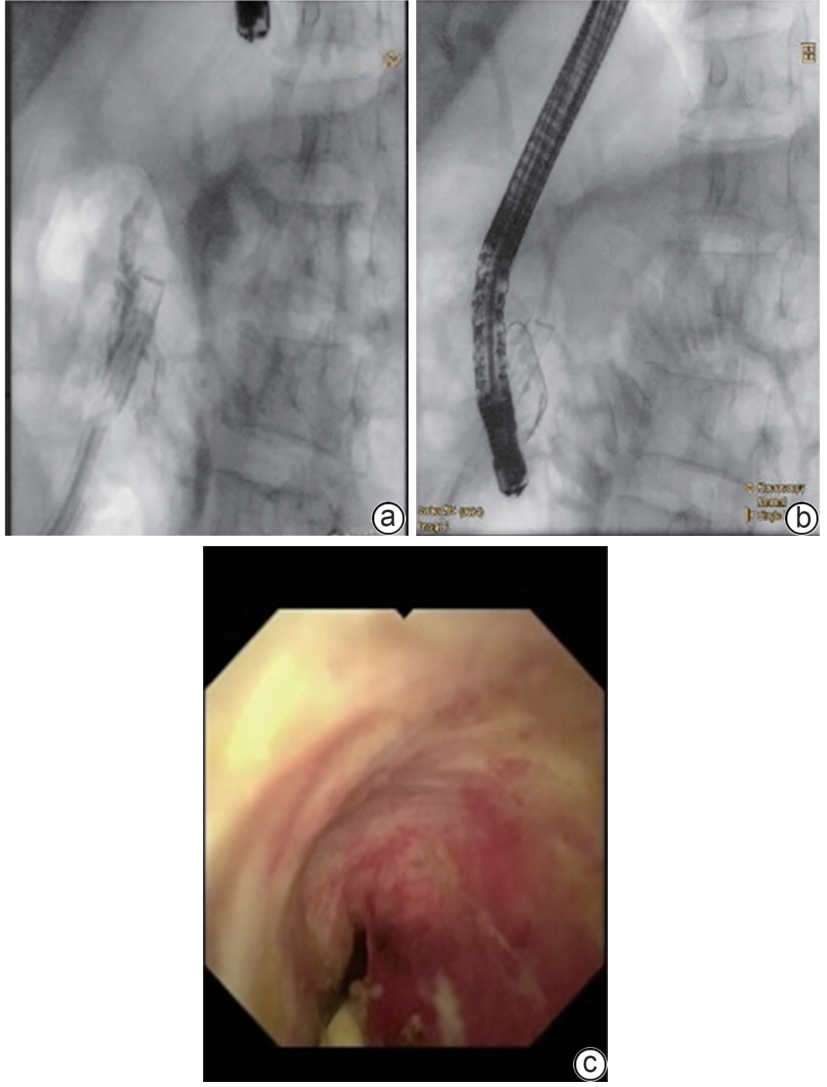

Successful treatment of biliary fistula after Beger surgery by oral choledochoscopy-assisted percutaneous-endoscopic rendezvous technique: A case report

Yuxin WANG, Weigang GU, Zheng JIN, Xiaofeng ZHANG

2025, 41(2): 333-336. DOI: 10.12449/JCH250220

Abstract(927) HTML (261) PDF (4794KB)(52)

Abstract:

Duodenum-preserving pancreatic head resection, also known as Beger surgery, has a high incidence rate of bile duct injury after surgery, while the treatment modality for bile duct injury depends on the severity of the injury, and endoscopic therapy is often challenging in case of severe bile duct injury. Recently a patient with biliary fistula after Beger surgery was admitted to Affiliated Hangzhou First People’s Hospital, Westlake University, and successful diagnosis and treatment were achieved through oral choledochoscopy-assisted percutaneous-endoscopic rendezvous technique.